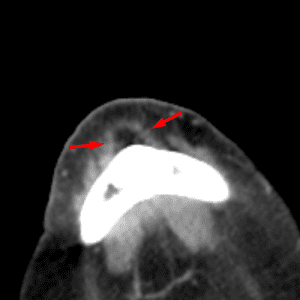

Mendosal Suture

Mimicking a fracture